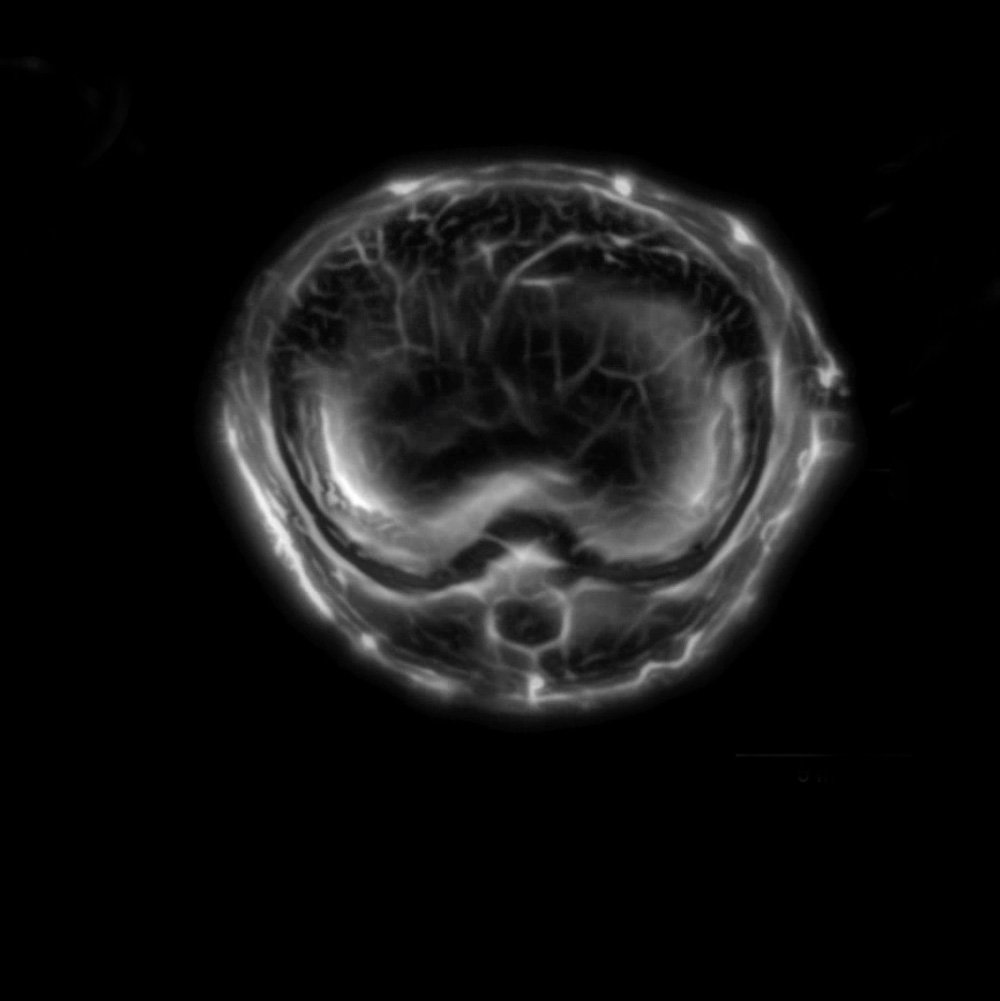

Wang and his colleagues have been developing photoacoustic tomography for more than 10 years. This latest iteration adds increased speed and panoramic views to the imaging technology's repertoire. The engineers have built a circular ultrasonic detector and a fast data-acquisition system that can triangulate the origin of an ultrasonic wave from anywhere within the body of a small animal. And with the help of a fast laser, the upgraded device can image the full cross-section of an adult rat 50 times per second, providing detailed movies of its inner workings with 120-micrometer resolution.

"The panoramic effect provides information from all directions and all angles, so you do not lose any information from each laser shot," Yao says. "You can see the dynamics of the body in action—the pumping of the heart, the dilation of arteries, the functioning of various tissues."

The paper describes how the engineers use these abilities to track cancerous melanoma cells as they travel through the blood vessels of a mouse. They also demonstrate the ability to watch the entire brain in real time.